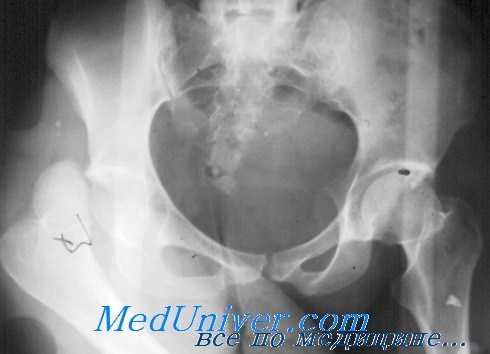

Если нога в момент удара находится в положении отведения, то возникает перелом задней стенки вертлужной впадины, а в положении приведения происходят просто вывихи бедра. При заднем вывихе нога принимает характерное положение — согнута в тазобедренном суставе, приведена и ротирована кнутри, при этом активные движения невозможны. Однако при тяжелом переломе задней стенки вертлужной впадины такие симптомы могут отсутствовать.

К сопутствующим повреждениям относится паралич седалищного нерва, чаще только малоберцовой ветви, что требует неврологического обследования. Передние вывихи встречаются реже (5%) и происходят вследствие форсированного отведения и наружной ротации, что придает конечности характерную деформацию. Рентгенологические признаки вывиха или перелома со смещением хорошо видны на снимках в передне-задней проекции.